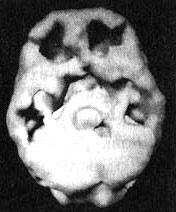

Трехмерное изображение поверхности — вид сверху. Обратите внимание на многочисленные отверстия в коре головного мозга.